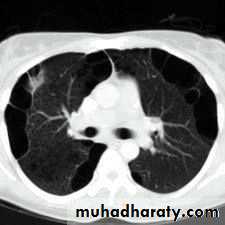

Area of hypertranslucensy (pneumothorax)

What is the difference?

(emphysematous bullae) (pneumothorax)

Hydated cyst (simple)